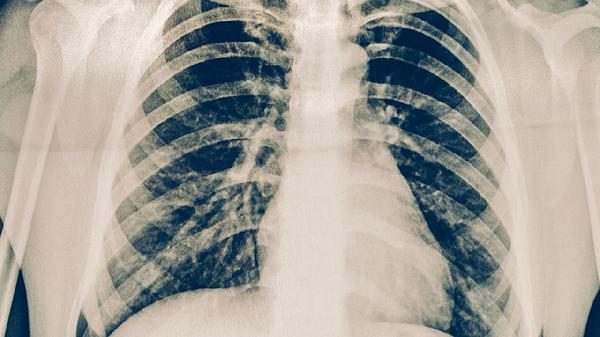

肺結(jié)核患者早期多表現(xiàn)為持續(xù)性干咳,隨著病情進(jìn)展可出現(xiàn)咳痰??人钥赡芘c結(jié)核分枝桿菌感染導(dǎo)致肺部組織發(fā)生炎癥反應(yīng)有關(guān),通常伴隨午后低熱、夜間盜汗等癥狀?;颊呖稍卺t(yī)生指導(dǎo)下使用異煙肼片、利福平膠囊、吡嗪酰胺片等抗結(jié)核藥物進(jìn)行治療。

肺結(jié)核患者咳出的痰液多呈白色黏液狀,病情加重時(shí)可出現(xiàn)黃綠色膿性痰。咳痰可能與肺部病灶壞死液化有關(guān),通常伴隨乏力、食欲減退等癥狀?;颊咝枳襻t(yī)囑規(guī)范使用抗結(jié)核藥物,同時(shí)保持室內(nèi)空氣流通,避免痰液飛沫傳播。

肺結(jié)核引起的胸痛多表現(xiàn)為隱痛或鈍痛,咳嗽時(shí)疼痛加劇。胸痛可能與胸膜受累或肺部炎癥刺激有關(guān),通常伴隨氣促、消瘦等癥狀?;颊呖墒褂脤?duì)乙酰氨基酚片緩解疼痛,同時(shí)配合異煙肼片、乙胺丁醇片等抗結(jié)核藥物治療。

肺結(jié)核患者多為午后低熱,體溫一般在37-38℃之間,可伴有夜間盜汗。發(fā)熱可能與結(jié)核分枝桿菌釋放毒素引起機(jī)體免疫反應(yīng)有關(guān),通常伴隨全身乏力、體重下降等癥狀?;颊咝枳⒁庑菹?,在醫(yī)生指導(dǎo)下使用抗結(jié)核藥物,發(fā)熱嚴(yán)重時(shí)可臨時(shí)服用布洛芬混懸液退熱。